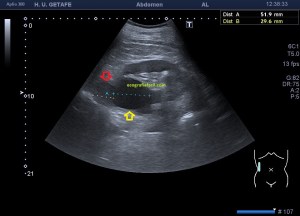

En la imagen 3 ves una imagen de un lipoma, mide 7 cms, la huella de la sonda mide 5cms, la «panoramic view» posee una regla centimetrada que sigue el contorno de la imagen, justo en la profundidad de la misma y lo marca la flecha amarilla. La profundidad la marca la flecha roja y la flecha blanca marca el rango centimetral de los 5cms, fíjate que la línea blanca es ligeramente mayor cada 5 cms. Sirve de referencia, como en la imagen 4 donde ves una colección en el glúteo de más de 10 cms.